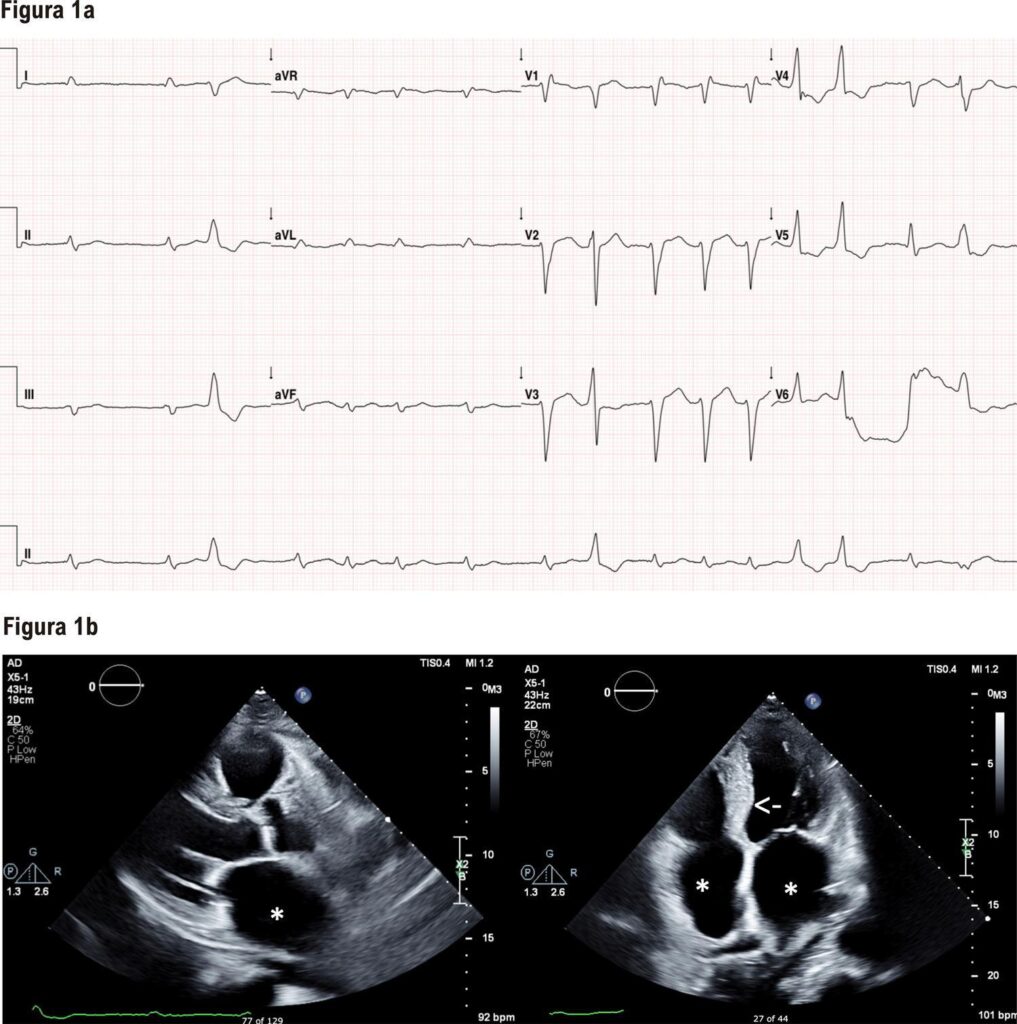

Um paciente de 90 anos buscou atendimento com queixas e exame físico compatíveis com insuficiência cardíaca descompensada. Eletrocardiograma demonstrou fibrilação atrial e baixa voltagem em derivações dos membros, e ecocardiograma identificou dilatação biatrial, além de discreto aumento das espessuras parietais e do diâmetro do ventrículo esquerdo. A ressonância magnética demonstrou realce tardio subendocárdico confirmando a suspeita de amiloidose cardíaca. Com eletroforese e imunofixação de proteínas séricas e urinárias negativas e cintilografia com pirofosfato positiva, foi confirmado diagnóstico de amiloidose transtirretina. O sequenciamento do gene da transtirretina não detectou mutações, sendo caracterizado um caso de amiloidose transtirretina selvagem.